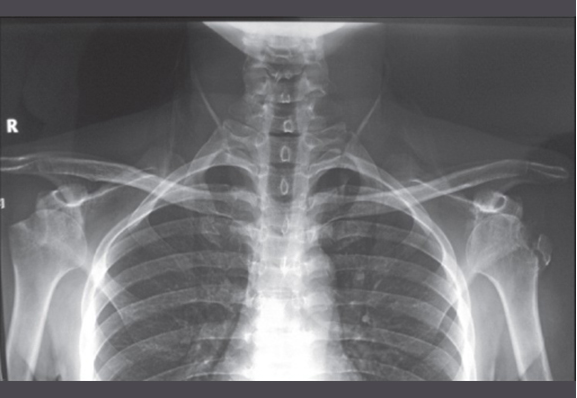

Image from OpenI – Licensed by CC